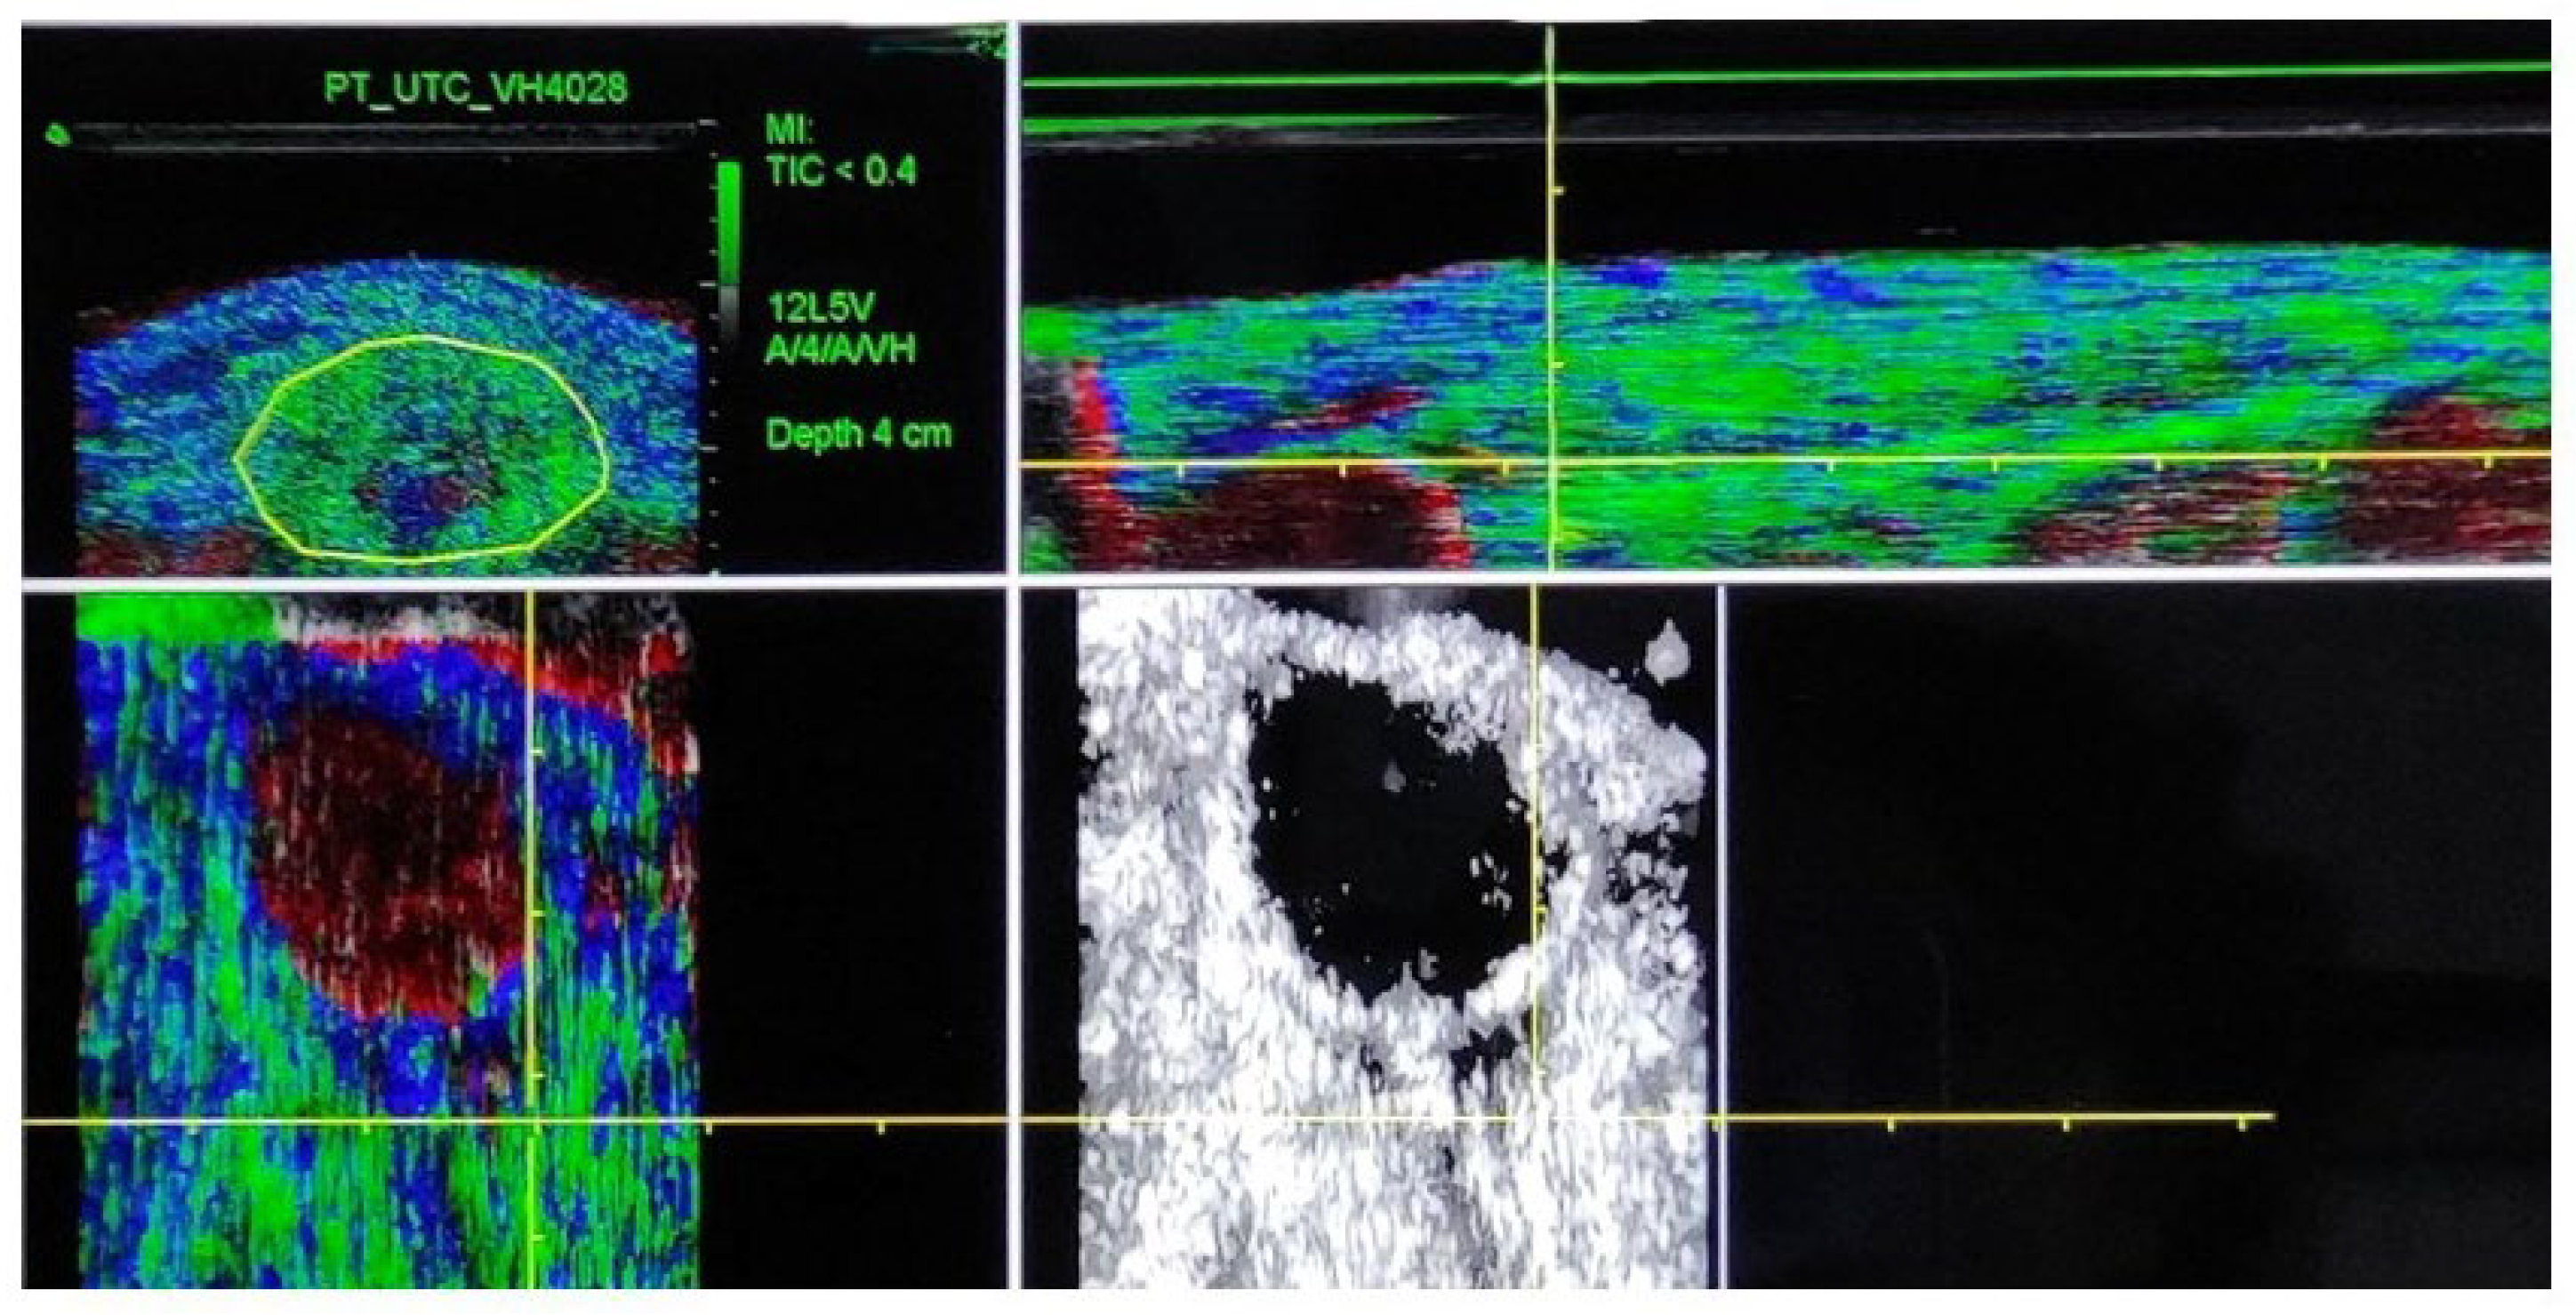

2.3. Procedure

- van Schie, H.T.M.; de Vos, R.J.; de Jonge, S.; Bakker, E.M.; Heijboer, M.P.; Verhaar, J.A.N.; Tol, J.L.; Weinans, H. Ultrasonographic tissue characterisation of human Achilles tendons: Quantification of tendon structure through a novel non-invasive approach. Br. J. Sports Med. 2010, 44, 1153–1159. [Google Scholar] [CrossRef]

- Van Schie, H.; Docking, S.; Daffy, J.; Praet, S.; Rosengarten, S.; Cook, J.L. Ultrasound tissue characterization, an innovative technique for injury-prevention and monitoring of tendinopathy. Br. J. Sports Med. 2013, 47, e2. [Google Scholar] [CrossRef]